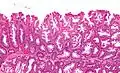

Moyen grossissement x100: Adénome festonné sessile.

La partie profonde des glandes est souvent élargie, a tendance à se diviser en deux ou trois branches et à s’horizontaliser, c'est-à-dire à se disposer parallèlement à la musculaire muqueuse et non pas perpendiculairement à elle, comme dans les polypes hyperplasiques conventionnels et les adénomes festonnés traditionnels.